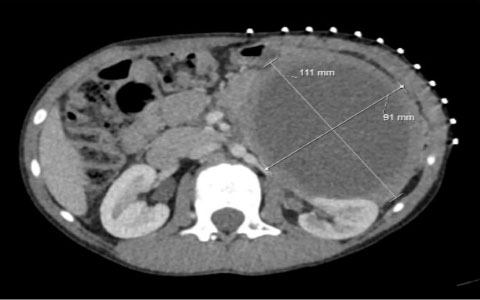

A previously well 9-year-old boy presented with intermittent left upper quadrant pain, anorexia, and weight loss over six months. His past medical history was significant for being born preterm at 34 weeks’ gestation and requiring ventilatory support as a neonate. Computed tomography (CT) scan (Figure 1 and Figure 2) showed a 10 cm encapsulated spherical mass appearing to arise from the pancreatic tail. The working diagnosis was a cystic pancreatic tumour, and he was referred for further management.

Figure 2: CT axial view showing the cyst and its relations to the left kidney and vasculature.